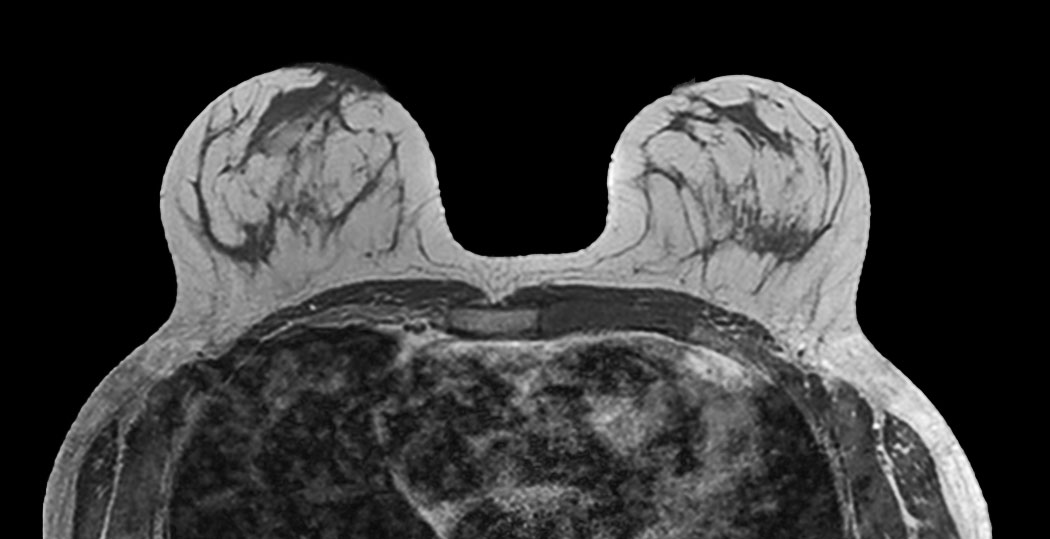

Breast imaging using SmartExam

Used Solution